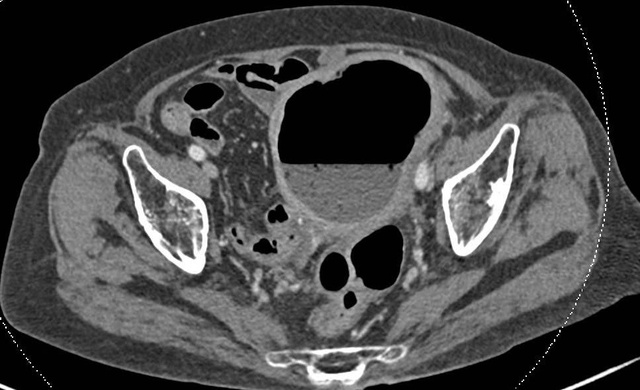

Phim chụp CT cho thấy tử cung có kích thước lớn bất thường, chứa nhiều khí và dịch. Ảnh: FV

Cụ M.T.M. (88 tuổi, TP.HCM) được người nhà đưa đến Bệnh viện FV trong tình trạng sốt, đau bụng âm ỉ không dứt, âm đạo tiết dịch mủ. ThS.BS Lê Đức Tuấn - Khoa Ngoại tổng quát chỉ định chụp CT ổ bụng. Hình ảnh cho thấy tử cung to bất thường, chứa đầy dịch và khí. Cụ được chỉ định nội soi đại tràng và lòng tử cung, kết quả khẳng định: phân xuất hiện trong khoang tử cung – dấu hiệu của rò âm đạo trực tràng, nếu không được xử lý kịp thời sẽ nguy hiểm tới tính mạng.